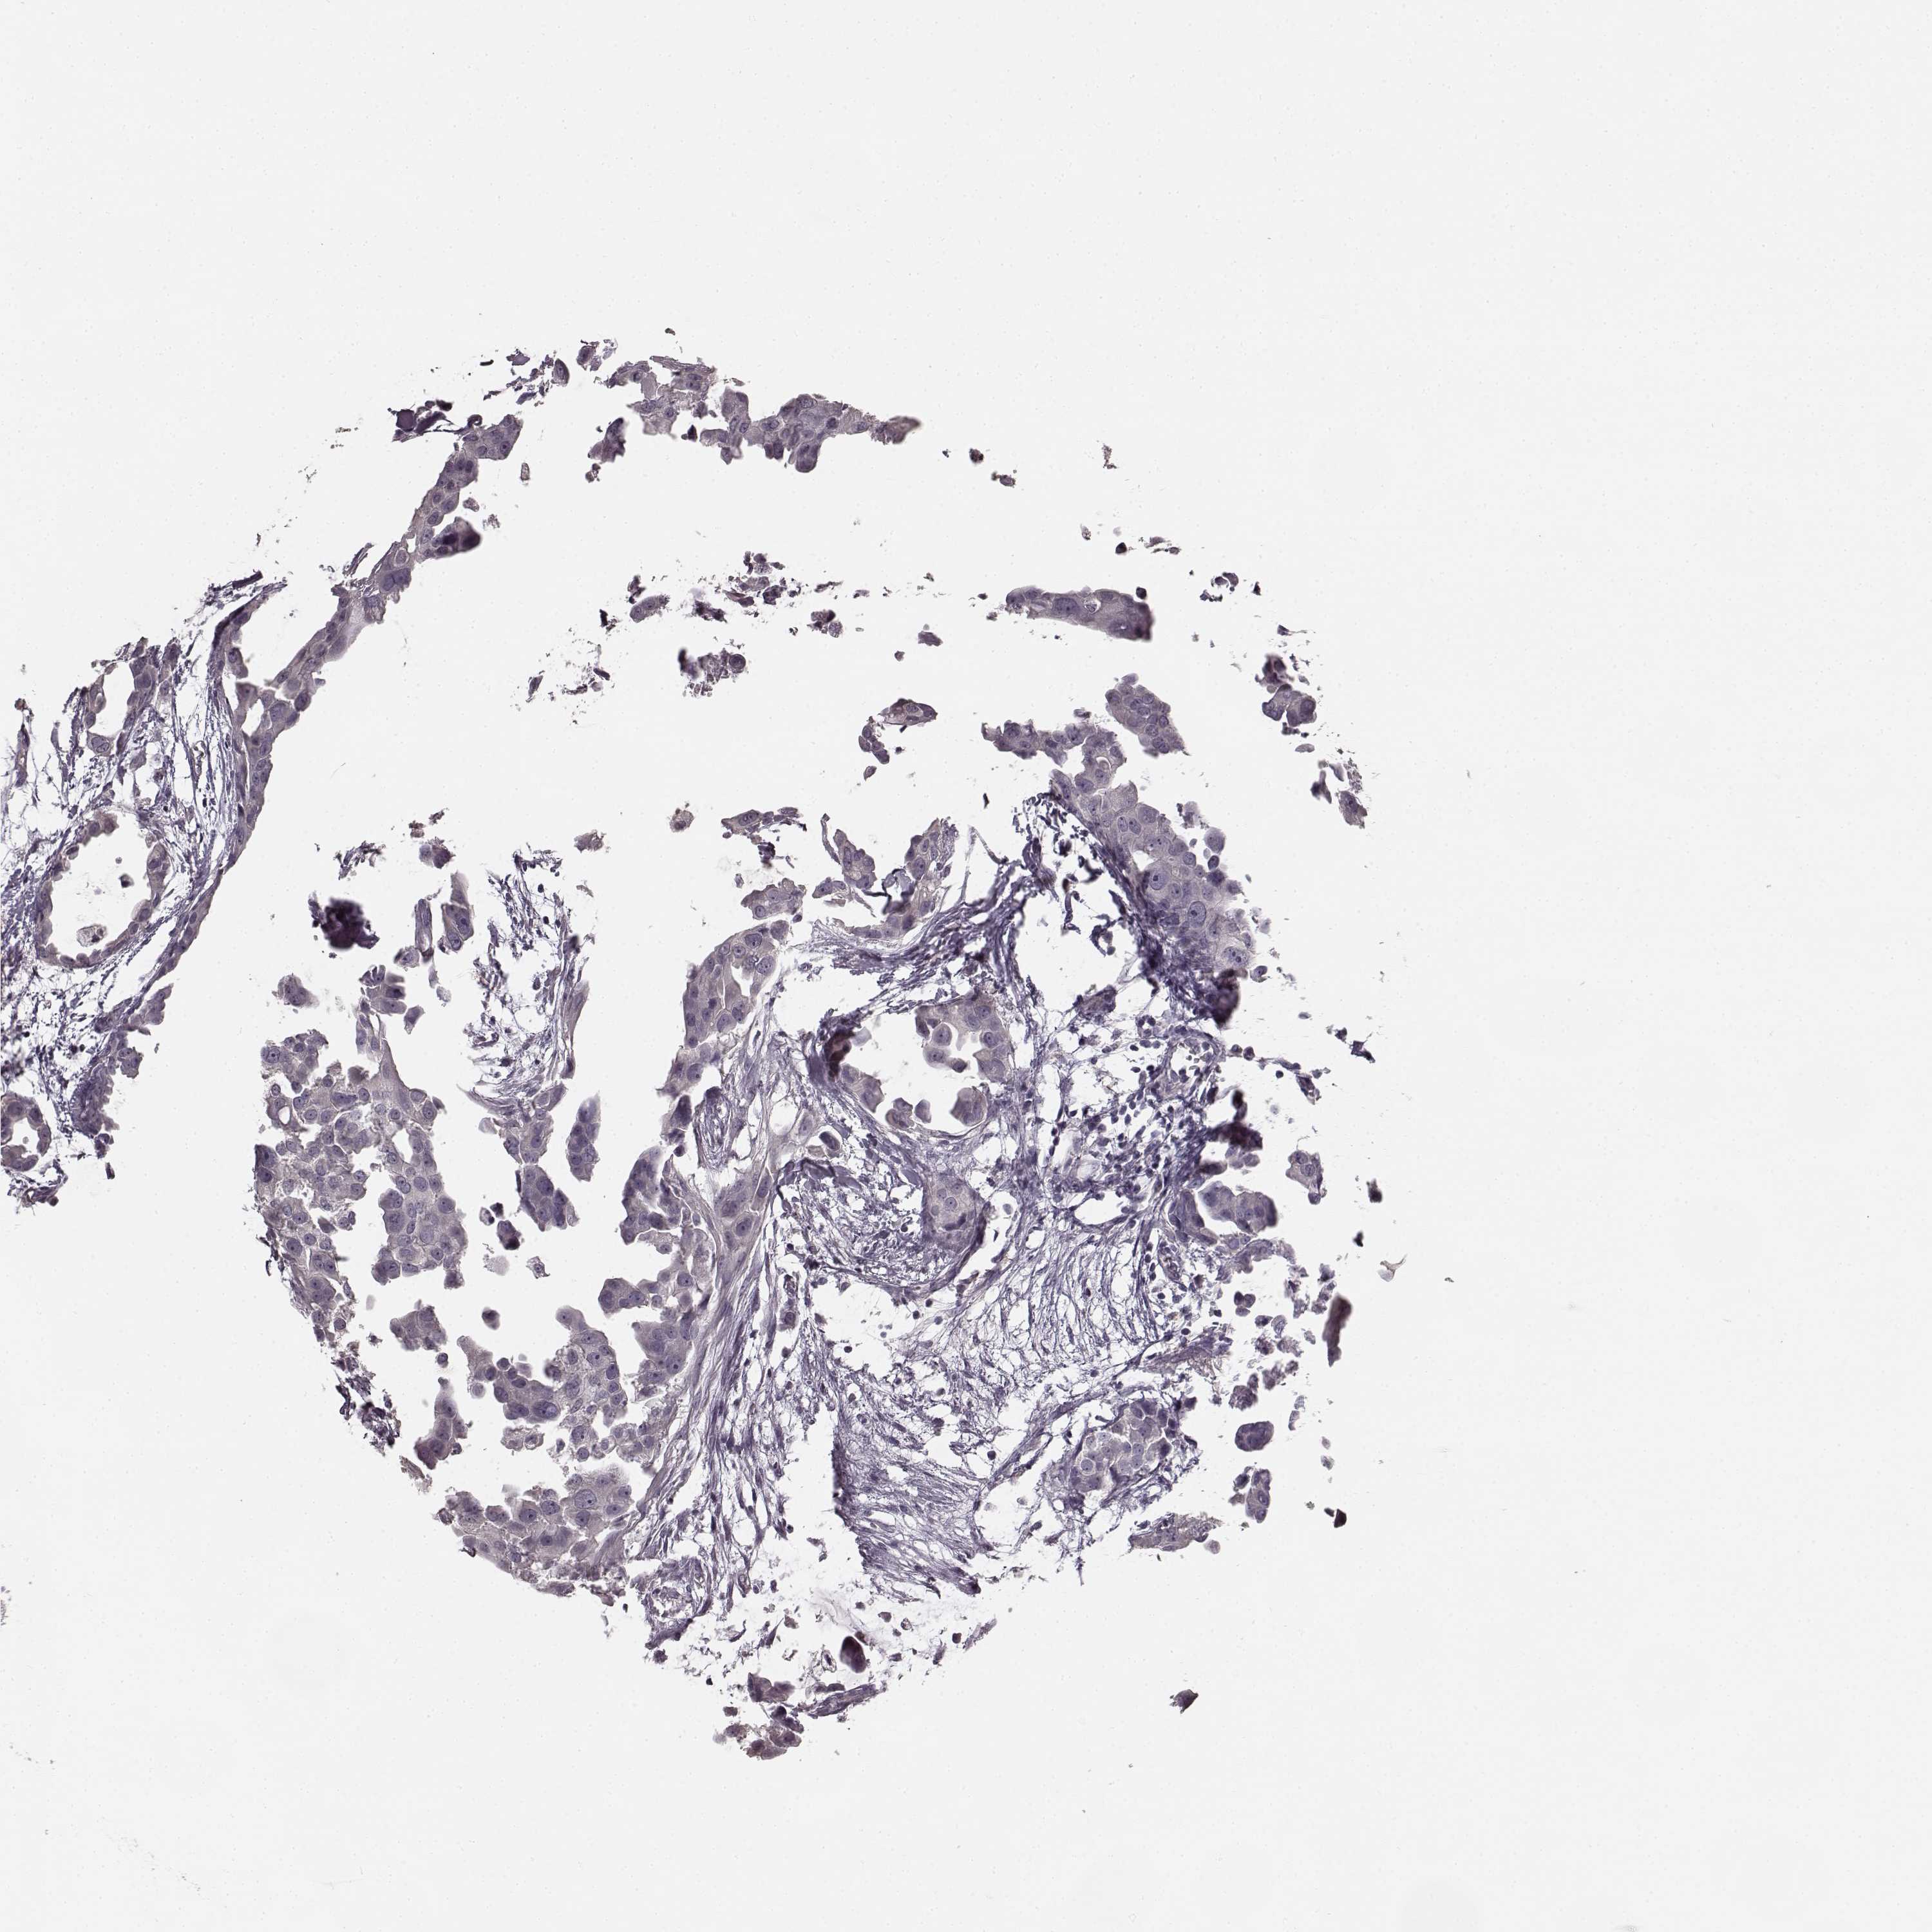

CANCER BREAST CANCER Show tissue menu

BRCA TCGA BRCA VALIDATION PROTEIN EXPRESSION